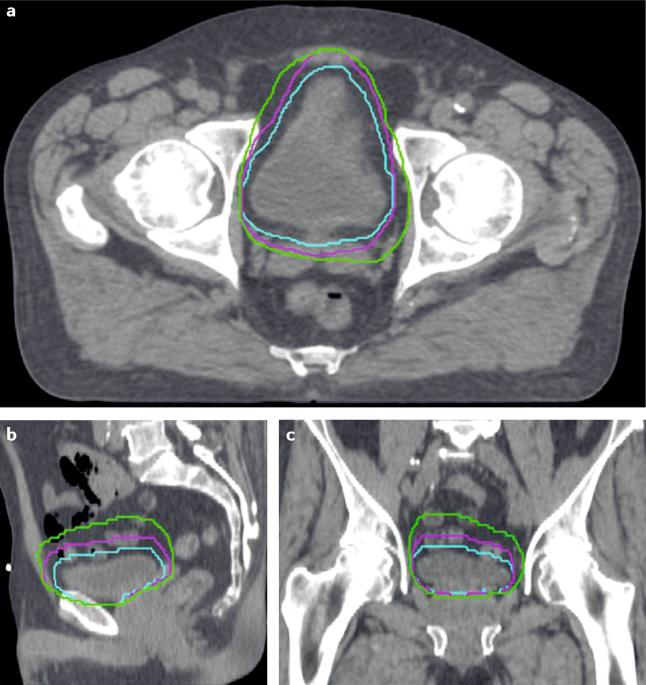

Get Bladder Cancer Ct Scan Pictures. Bladder cancer is any of several types of cancer arising from the tissues of the urinary bladder.1 symptoms include blood in the urine, pain with if invasive or high grade (includes carcinoma in situ) cancer is detected on turbt, an mri and/or ct scan of the abdomen and pelvis or urogram and ct. This is known as the grade, and your doctor may describe bladder cancer as either low.

What is a ct scan? Less commonly, an mri (magnetic resonance imaging) scan may be used to check for bladder cancer. Ct scans can also be used to guide a biopsy needle into a suspected tumor. The spread of cancer to lymph nodes is best evaluated by ct scan or during surgery.